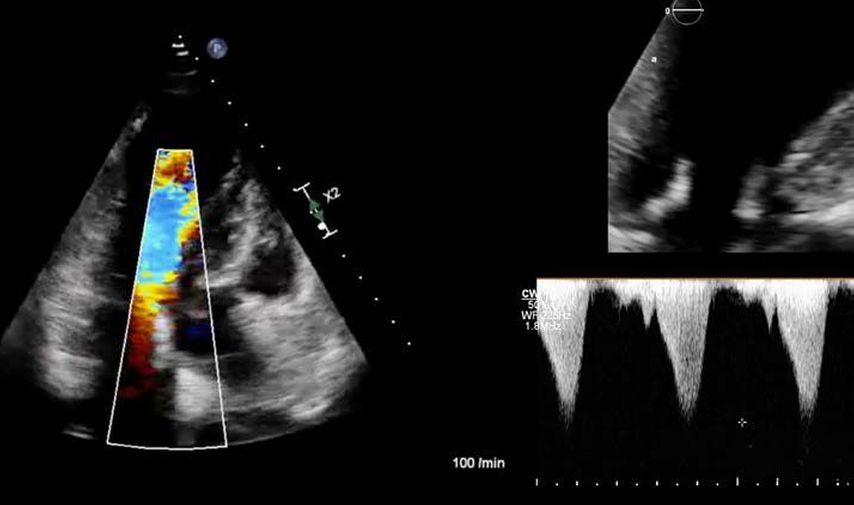

Bei der hypertrophen CMP gibt es die Besonderheit, dass versucht werden muss, einen Ausflusstraktgradienten (LVOTO) zu messen, da dieser für die Prognose und Therapie relevant ist.1 Eine neue Therapie der hypertrophen obstruktiven CMP (HOCMP) sind kardiale Myosininhibitoren. Diese können zu einem „reverse remodeling“ des Herzens führen und Parameter, wie den „strain“, neben der Reduktion des Ausflusstraktgradienten unter Therapie deutlich verbessern.1,8,9

1. Fall: HCMP vs. HOCMP, männlich 52a

Der erste Fall beschäftigt sich mit einem Patienten mit einer hypertrophen Kardiomyopathie (HCMP). Er gibt eine deutliche Belastungsdyspnoe sowie einen ausgeprägten Leistungsknick an. Es wurde infolgedessen eine Untersuchung mittels standardisierter Echokardiografie inklusive „strain imaging“ durchgeführt. Der globale longitudinale „strain“ (GLS) mit –16% in Ruhe war gering reduziert. Es konnte kein relevanter LVOT-Gradient in Ruhe nachgewiesen werden. In der Belastungssituation (Handgrip, Valsalva, Kniebeugen und als Vorbereitung zur Untersuchung ein ausgiebiges Frühstück und Kaffee sowie ein am Vorabend konsumiertes Bier) konnte bei Kniebeugen mit einer Herzfrequenz von 126/min ein Spitzengradient bis 52mmHg dargestellt werden. Somit ergibt sich die Diagnose einer HOCMP mit einem belastungsinduzierten Gradienten. Bei bereits bestehender und ausgereizter Therapie unter Betablocker besteht die Indikation zur Therapie mittels des kardialen Myosininhibitors Mavacamten (Klasse-IIa-Empfehlung laut ESC).1 Darunter verbesserte sich die klinische Situation des Patienten deutlich, der Patient konnte uneingeschränkt Sport ausüben. Über die Zeit kam es zu einer geringen Reduktion der LV-Masse und einer geringen Zunahme des LV-„strain“. Die Belastungssituation zeigte durchwegs normale „strain“-Werte mit –20% (mit regionaler Reduktion bei Myokardwandverdickung im Sinne einer Hypertrophie). Die myokardiale Arbeit beim konkreten Patientenfall ist ebenso in Ruhe im grenzwertigen und unter Belastung im guten Normalbereich.6,8,9 Der Patient ist derzeit unter 5mg Mavacamten einmal täglich optimal eingestellt. Die EF in Ruhe ist konstant bei 50–55%. In Video 2 werden unterschiedliche Gradienten dargestellt, um eine HOCMP mit LVOTO von z.B. einer Mitralklappeninsuffizienz zu unterscheiden.Die Verdachtsdiagnose wurde mithilfe der Echokardiografie gestellt und durch das septal betonte „patchy“ LGE im MRT bestätigt.1,5